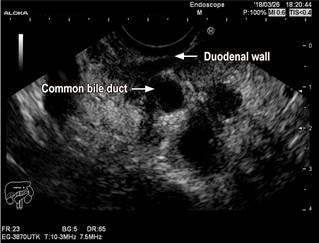

Endoscopic ultrasound (EUS) has been proposed as the diagnostic technique of choice due to its greater sensitivity (86%) and the added value of making it possible to take samples for histological analysis purposes33. Imaging findings in EUS show chronic pancreatitis changes based on the Rosemont’s criteria, which allow it to have a good diagnostic performance34. As it happens in other imaging studies, a thickening of the second part of the duodenum and heterogeneity of the dorsocranial portion of the pancreatic head findings have been reported with this imaging technique. In addition, several authors have described a pathognomonic finding using EUS in advanced stages of groove pancreatitis: hyperechoic thickening of the duodenal wall in the groove area with anechoic ductal structures extending towards the head of the pancreas. This hyperechoic lesion correlates with myoadenomatous proliferation and adjacent fibrosis of the pancreas10,27. In our patient, a significant edema in the duodenal wall and dilatation of the common bile duct were observed in the EUS (Figure 3).